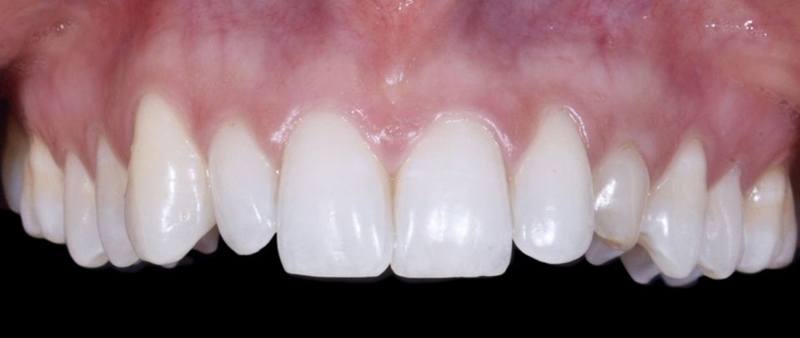

口外检查中,面部评价显示面部对称、比例匀称。微笑分析显示中线矢状面与微笑中线重合,上切牙和尖牙的暴露率为90%(图1)。微笑还显示侧切牙形状不同,与对侧恒尖牙相比,左上乳尖牙更短、更窄、颜色更黄(图2-4)。

Fig. 2: Frontal view of the patient’s smile.

Fig. 3: Right lateral view of the patient’s smile.

Fig. 4: Left lateral view of the patient’s smile.

Fig. 5: Intraoral frontal view

Fig. 6: Intraoral view: The discrepancy between upper canines and lateral incisors is clear. Note that the deciduous tooth is shorter than the contralateral, both at the occlusal and at the gingival side.

Fig. 7: Magnification of the deciduous tooth: A wide amount of keratinized gingiva is shown.